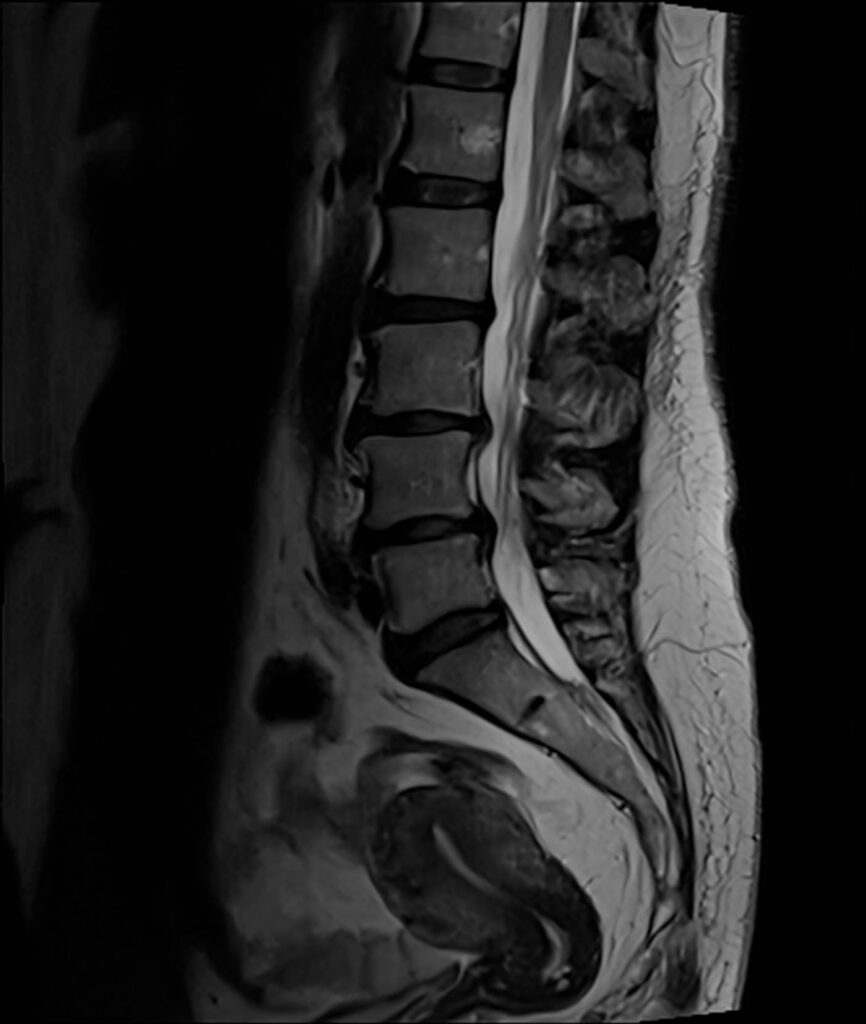

Zwężenie odcinka lędźwiowego

Zwężenie odcinka lędźwiowego to stan, w którym kanał kręgowy zwęża się w dolnej części pleców (lędźwiowej), wywierając nacisk na rdzeń kręgowy i korzenie nerwowe. Może to prowadzić do bólu, drętwienia, mrowienia, osłabienia i trudności w chodzeniu lub staniu.

Zwężenie odcinka lędźwiowego może być spowodowane różnymi czynnikami, w tym starzeniem się, zapaleniem stawów, przepuklinami dysków, urazami kręgosłupa i nowotworami. Objawy mogą się różnić w zależności od ciężkości zwężenia, ale mogą obejmować ból pleców, ból nóg, drętwienie lub osłabienie nóg oraz trudności z równowagą lub koordynacją.